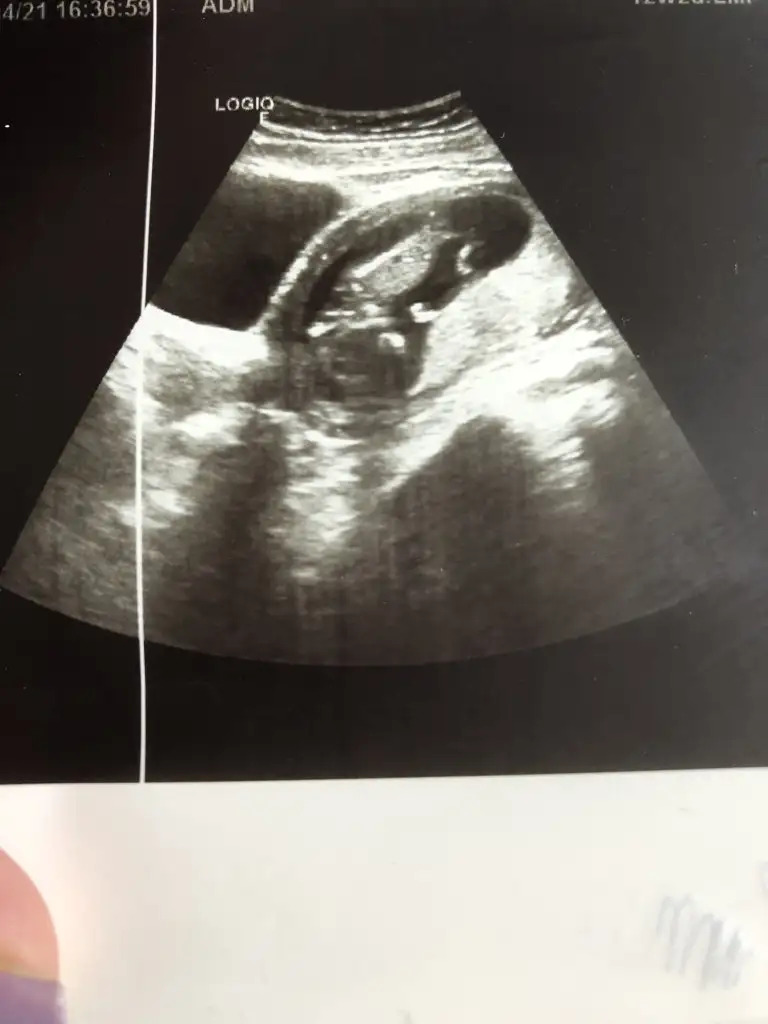

Bu net kız canimIkra meyra 16 haftalık bacak altından sence hangisine yatkın

Kız görünüyorKızlar hiç anlamıyorum şu nub işlerinden bana da bakarmısınız 12+2 ultrason resimleri doktor hiç birşey söylemedi tahmin var mı

Hayırlısı sağlıkla gelsin inşallah bakalım ne zaman belli olucak sabırsızlanıyorumKız görünüyor